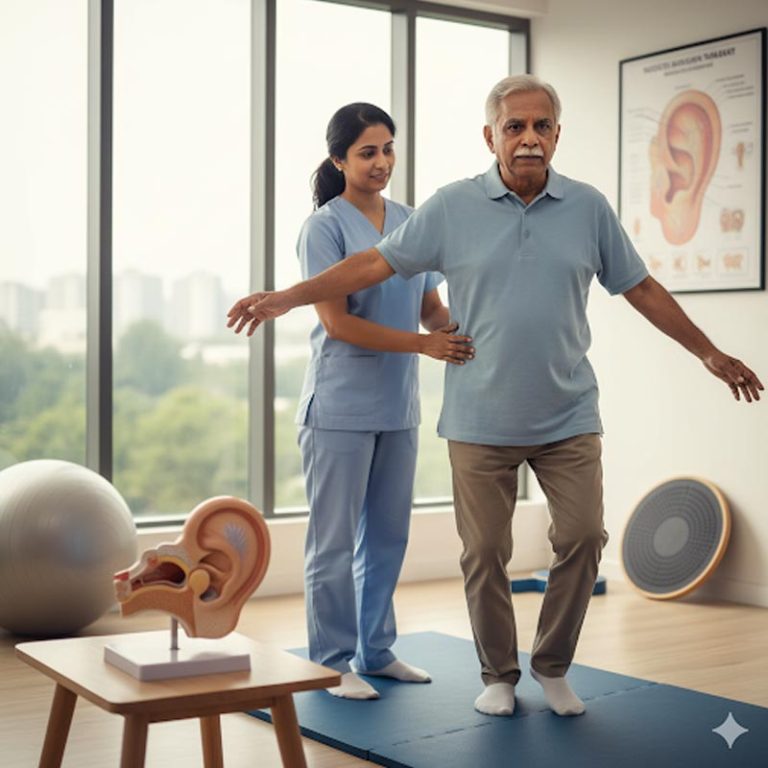

Vestibular Rehabilitation Therapy (VRT) is an exercise-based program used to treat a variety of vestibular...

Geriatric physiotherapy is a specialised field of physical therapy that focuses on the unique physical...

Orthopedic Physiotherapy focuses on the treatment of musculoskeletal conditions involving bones, joints,...